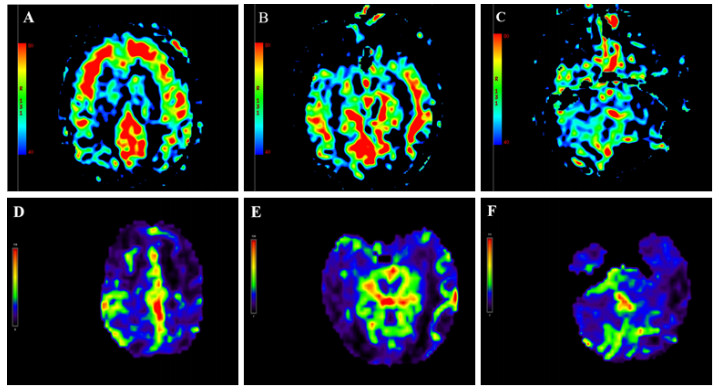

患者入院后即行血液灌流(3次/d,共2 d)清除毒物、连续性肾脏替代治疗纠正内环境紊乱、血管活性药物维持血压、补液促进毒物排泄及对症支持等治疗。中毒后第5天,患者仍深昏迷,GCS评分2T(E1VTM1)。复查头颅CT:双侧基底节区对称性低密度灶,较前片明显,见图 1B。中毒后第9天,意识状况仍无改善,检查头颅MRI:双侧额顶颞枕叶皮层下、基底节区、桥臂多发异常信号,伴脑肿胀,考虑中毒性脑病,见图 1D~图 1H;磁共振动脉自旋标记(arterial spin labeling, ASL):两侧额颞叶皮层下白质区对称性灌注增高,两侧基底节、小脑、枕顶叶对称性灌注减低,符合中毒性脑病改变,见图 2A~图 2C。针对意识障碍治疗予纳洛酮静脉滴注;针对脑水肿予20%甘露醇静脉滴注(每次150ml,第1周每8小时1次,第2周每12小时1次),甲泼尼龙静脉注射(每次40mg,第1周每日2次,第2周每日1次)。中毒后第7天行床旁气管切开,中毒后第15天呼吸循环稳定,停用呼吸机,但仍处于昏迷状态,无气道自洁能力,GCS评分5分(E2V1M2)。中毒后第15天复查头颅CT:双侧基底节区病灶较前密度减低,新增小片状高密度影,提示小出血灶,见图 1C。

| 注:(A-C)中毒第9天,头颅ASL显示双侧额叶、颞叶皮层下白质区对称性灌注增高,双侧小脑半球灌注减低;(D-F)中毒后第6月头颅ASL显示双侧额叶、枕叶、小脑半球灌注弥漫性减低;图中红色代表高灌注,蓝色代表低灌注,黄色代表两者之间 图 2 本例患者头颅ASL灌注成像动态变化 |

患者中毒后第20天出院,并转至本地康复医院继续治疗,方案包括高压氧促进脑功能恢复、药物预防癫痫发作,辅以低频电刺激、电动起立床训练、针灸等康复治疗。康复过程中患者持续经鼻饲进食,大小便无法自控,中毒后第3个月GCS评分7分(E2V2M3)。坚持以上康复方案,中毒后第6个月,GCS评分10分(E3V3M4)。复查头颅MRI:双侧额顶枕叶皮层下可见少许斑点片状及条片状DWI稍高信号影,较前高信号减低,范围缩小,脑室系统明显扩大,皮层萎缩,见图 1I ~图 1J。磁共振ASL:双侧额顶枕叶、小脑半球灌注弥漫性减低,损害范围较前扩大,见图 2D~图 2F。动态随访,中毒后第10个月,患者意识状况稍改善,能自主睁眼,简单应答,对刺痛能明确定位,能经口进食,GCS评分12分(E4V3M5)。随访至中毒后第15个月,患者神经功能较前不再有显著变化。

目前关于中毒性脑病局部脑血流变化的研究较少,本例患者进行了脑灌注检查,以期为中毒性脑病提供更多具有特征性的诊断依据。有研究[12]对3例甲苯中毒性脑病患者进行了磁共振ASL检测,结果发现中毒组所有感兴趣区平均脑血流量值和正常对照组无差异。然而,川玲等[11]通过核素脑血流灌注显像的方法对46例中毒性脑病患者进行观察,发现大部分患者存在不同程度的局限性或弥漫性脑血流灌注减低。本例哒螨灵中毒患者磁共振ASL检测显示急性期不同部位脑血流变化趋势不一,表现为双侧额颞叶皮层下白质区对称性高灌注,基底节、小脑、枕顶叶对称性低灌注,6个月后复查发现全脑多部位呈弥漫性低灌注。通常,中毒性脑病伴随脑细胞水肿和血管内皮细胞肿胀,影响脑的血液循环,导致低灌注。本例中毒性脑病急性期部分脑白质区呈现高灌注,其原因尚不明确,可能与中毒后这些区域脑实质发生充血肿胀、血流速度增快有关[13]。